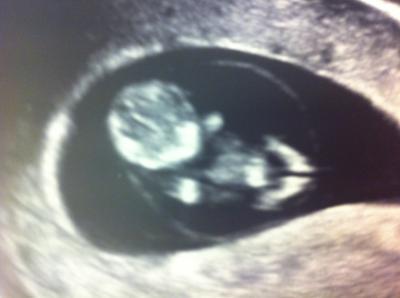

Wie versprochen mein US Bild von gestern...

... voll toll ich bin so stolz auf mein Krümmel, er/sie/es hat sich da klasse gezeigt... war da 11+1 und das baby ist 3,2cm groß

Das ist aber ein schönes Bild!! Man kann das Kleine wirklich gut erkennen.